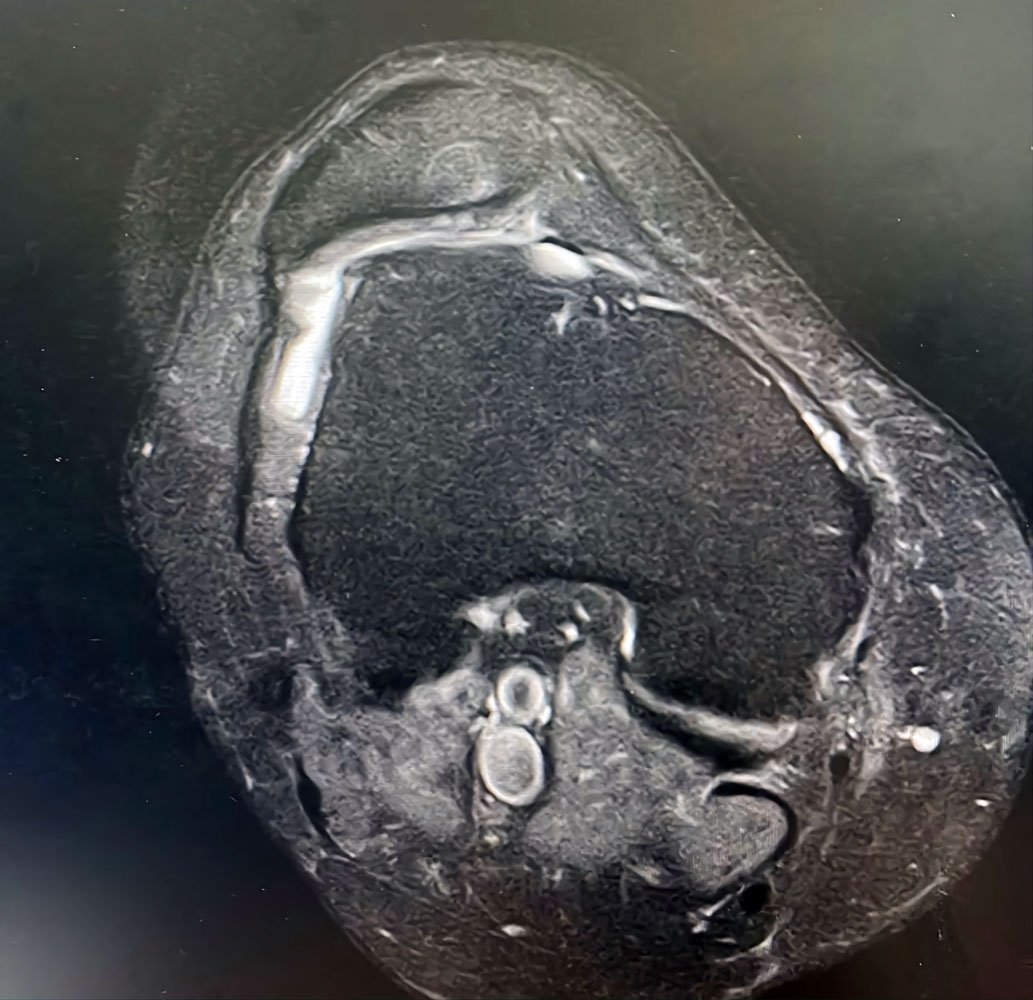

Пироговский Центр в сотрудничестве со Сколковским институтом науки и технологий, ООО «Сбермедии» и ООО «Иммерсмед» продолжил исследовать возможности применения цифровых инноваций в медицине. Ведутся проекты по использованию современных технологий, включая машинное обучение, для обработки результатов магнитно-резонансной томографии и электроэнцефалографии. Цель проекта — изучение причин и своевременная диагностика эпилепсии, что позволит не только приоткрыть тайны функциональных структур головного мозга, но и вовремя начать прием наиболее подходящих медикаментов, провести нейрохирургическую операцию, повысив тем самым вероятность полного излечения пациентов.

- Современная нейровизуализация (МРТ, ОФЭКТ, SISCOM)

Внедрен современный протокол диагностики эпилептогенных очагов головного мозга — протокол SISCOM (Subtraction Ictal SPECT Co-Registered to MRI)